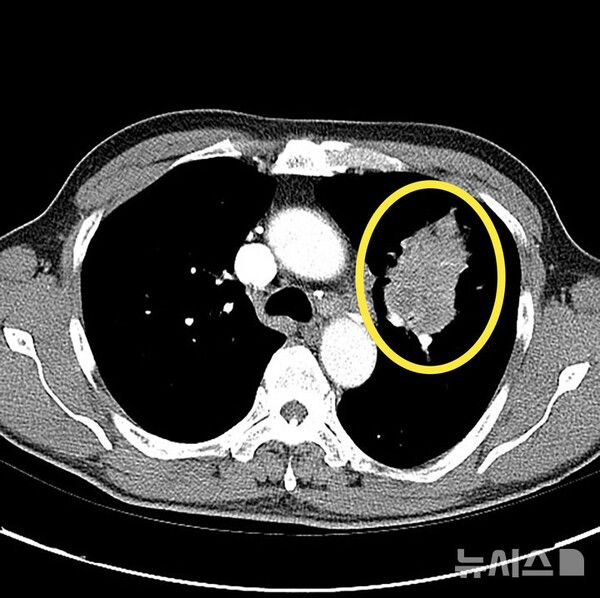

사진 = 뉴시스

폐암 진단은 보통 흉부 X-레이로 폐의 이상 여부를 확인하는 것에서 시작한다. 그러나 초기 병변은 잘 보이지 않아 저선량 흉부 CT가 정밀 진단하게 된다. CT에서 폐 결절이 발견되면 조직 검사로 확진한다. 폐암이 진단된 경우 추가 영상검사를 통해 병기를 판정한다. 최근에는 분자유전학 검사로 유전자 변이를 확인해 환자 맞춤형 치료 방침을 정한다.